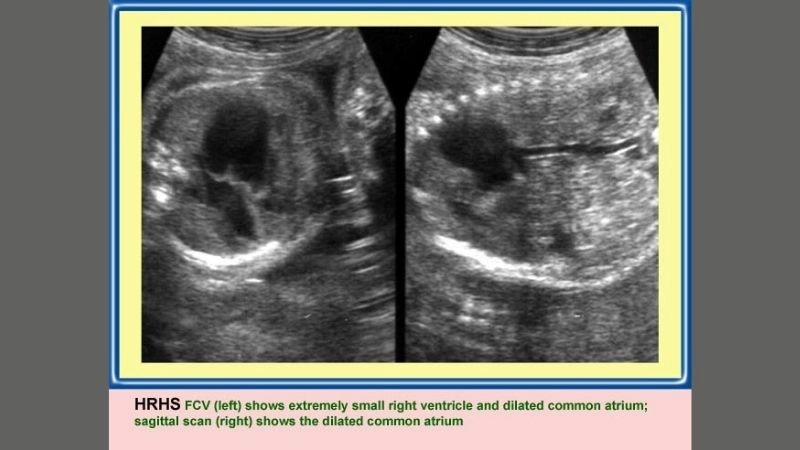

Images visual examples of hypoplastic right heart syndrome (HRHS)

Hypoplastic right heart syndrome (HRHS) is a rare congenital heart defect where the right side of the heart is underdeveloped, impairing blood flow to the lungs.